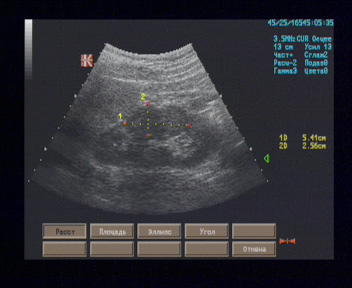

Левая почка 112 х 51 мм, положение и форма типичные, контуры заднелатерального края в проекции среднего сегмента на участке 5 см имеют двугорбый вид, паренхима в этом месте утолщена до 25 мм, однородная, равномерно гипоэхогенная; на остальном протяжении контуры почки ровные, паренхима толщиной 18 - 20 мм, однородная, равномерно гипоэхогенная, кортико-медуллярная дифференцировка умеренно выражена, ЧЛС не расширена.

Эхографические признаки локальной дисплазии паренхимы левой почки. Рекомендована компьютерная томография левой почки с целью исключения новообразования.